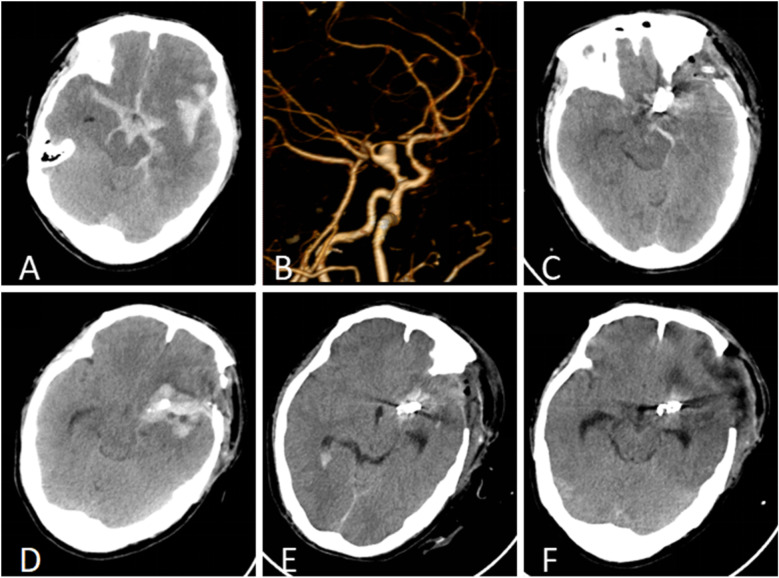

The simultaneous occurrence of intracranial aneurysms and intracranial arachnoid cysts is a rare clinical observation, with the majority of documented instances demonstrating ipsilateral presentation. In this report, we describe an atypical case involving the development of a secondary arachnoid cyst subsequent to the rupture of an intracranial aneurysm. Notably the cyst was situated contralaterally to the site of the aneurysm rupture and outside the surgical field. The patient's clinical history and imaging studies confirmedcorroborated the secondary nature of the cyst, which is postulated to have resulted from inflammatory responses triggered by a subarachnoid hemorrhage (SAH). The patient underwent neuroendoscopic partial resection of the cyst wall and lateral ventriculostomy, leading to a significant improvement in neurological dysfunction symptoms associated with the secondary arachnoid cyst. Follow-up cranial MRI demonstrated a substantial reduction in the cyst's volume, with no evidence of subsequent hydrocephalus or cyst enlargement. This case enhances the comprehension of the pathophysiological mechanisms underlying the formation of contralateral arachnoid cysts subsequent to aneurysm rupture and emphasizes the necessity of acknowledging arachnoid cysts as potential delayed complications associated with aneurysmal subarachnoid hemorrhage (aSAH).

颅内动脉瘤和颅内蛛网膜囊肿同时发生是一种罕见的临床观察,大多数记录的病例显示同侧表现。在这个报告中,我们描述了一个不典型的病例,涉及颅内动脉瘤破裂后继发性蛛网膜囊肿的发展。值得注意的是,囊肿位于动脉瘤破裂部位的对侧和手术野外。患者的临床病史和影像学检查证实了囊肿的继发性,推测是由蛛网膜下腔出血(SAH)引发的炎症反应引起的。患者接受了神经内窥镜部分切除囊肿壁和侧脑室造口术,继发性蛛网膜囊肿相关的神经功能障碍症状明显改善。后续颅脑MRI显示囊肿体积明显缩小,未见脑积水或囊肿增大。本病例加强了对动脉瘤破裂后对侧蛛网膜囊肿形成的病理生理机制的理解,并强调了将蛛网膜囊肿视为动脉瘤性蛛网膜下腔出血(aSAH)相关的潜在延迟并发症的必要性。